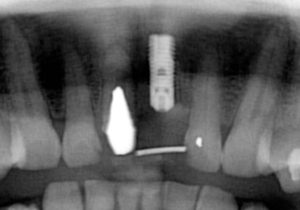

さて、この方は奥歯にインプラントを入れたのですが、あまり骨がなく普通の手術ではインプラント入れらません。そのため、インプラント手術だけならほとんど痛みはないのですが、上顎洞挙上術という難易度の高い手術を併用したため、手術後に痛みや腫れが若干出たようです。

奥歯にインプラントを入れ、前歯はホワイトニングやダイレクトボンディング、セラミックなどで修復しました。

長い間お疲れさまでした。この方は、前歯に審美的なインプラントを入れるため、抜歯後4ヶ月待ち、仮歯で歯肉が成熟するのを数が月待っていたりした為に、完成まで時間がかかってしまいました。

虫歯治療などは短期間で終えることができるのですが、歯ぐきをいじり出すとどうしても治癒期間が必要となり長くなってしまいます。それもこれも奇麗な仕上がりのために欠くことのできないものです。何卒ご容赦を!

- インプラント手術直後のレントゲン